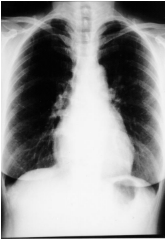

6. 僧帽瓣狹窄的胸部X光,如另 附圖一,常可見的影像有:(1) 主動脈影擴大。(2) 肺動脈影擴大。(3) 左心房擴大。(4) 右心室擴大。(5) 左心室擴大。 (A) (1)+(2)+(3) (B) (2)+(3)+(5) (C) (1)+(3)+(5) (D) (2)+(4)+(5) (E) (2)+(3)+(4)